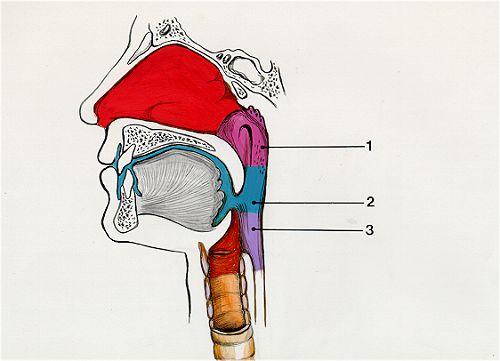

Larynx

Naso/oro/laryngo-phraynx

Epiglottis

Vocal folds (=vocal cords)

Esophagus

Trachae